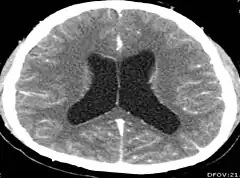

Intracranial hypertension – a build-up of pressure around the brain – is associated with neurocysticercosis and may be accompanied by other symptoms.[5] More common in extraparenchymal neurocysticercosis,[9] it is most frequently caused by buildup of cerebrospinal fluid (CSF) in the brain.[5][16] Hydrocephalus can be related to granular ependymitis, compression of the CSF pathways by cysts, cysticercotic arachnoiditis, and inflammation or cysts blocking ventricles.[5][9] Large subarachnoid cysts and cyst clumps can also cause a mass effect and intracranial hypertension, with or without hydrocephalus.[18] Intracranial hypertension can present as episodic loss of consciousness when moving the head, known as Bruns syndrome; [5] it may be subacute or chronic.[16] Cysticercotic encephalitis, which is a severe type of neurocysticercosis usually affecting younger women and children, can also cause intracranial hypertension.[9] Cysticercotic encephalitis is characterized by seizures, intracranial hypertension, clouding of consciousness, optic disc swelling, headache, reduction of visual acuity, and vomiting.[19][20]

CT scans and magnetic resonance imaging (MRI) give objective information about the number and pattern of lesions, the stage of healing, and how the immune system is responding to the parasites.[19] MRIs are better for evaluating different spatial planes and provides clearer images, which helps in identifying small lesions at the back of the brain or near the skull that may be missed on CT scans. CT scans are more sensitive at detecting calcium buildup in the brain due to its ability detect calcifications in the brain.[30]

Live vesicular cysts are small, round lesions with little swelling around them and do not need contrast for imaging. The tapeworm head (scolex) usually appears as an asymmetric nodule inside the cysts. Multiple live cysts with these heads corroborate the diagnosis. Once the cysts begin to break down (colloid cysts), their borders become unclear, they are surrounded by swelling and exhibit significant ring or nodular contrast enhancement. Calcified cysticerci are shown on CT scans as non-enhancing hyperdense nodules without swelling.[20]